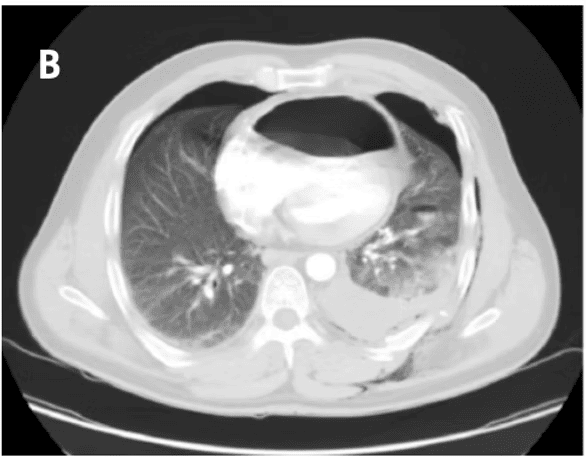

This article discusses the case of a 49-year-old man who sustained multiple injuries after falling from a height. These injuries included a diaphragmatic hernia, which is a tear in the diaphragm (the muscle separating the chest from the abdomen). In this rare instance, a portion of the stomach moved into the sac surrounding the heart (pericardium), causing pressure on the heart. This condition is known as cardiac tamponade.

CT scan for traumatic diaphragmatic hernia, Dr Saeed Hassan